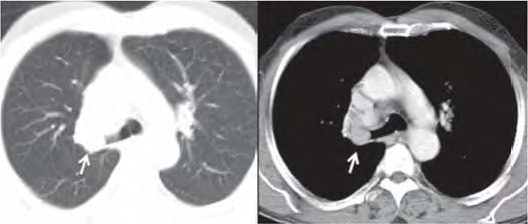

Uma paciente de 47 anos de idade, não tabagista, apresenta episódio de tosse e hemoptise. A tomografia computadorizada de tórax, realizada para investigação, evidenciou um nódulo pulmonar, com densidade de partes moles, de 2,1 cm, com obstrução do brônquio lobar superior direito, demonstrada nas imagens a seguir. Não há linfonodos mediastinais aumentados. A fibrobroncoscopia para investigação evidenciou uma lesão sólida em brônquio lobar superior direito, com obstrução total do brônquio, e aspecto em “dedo de luva”. As tomografias computadorizadas de abdome e de crânio não identificaram lesões metastáticas a distância. A biópsia endobrônquica demonstrou ser um carcinoide típico.

Acervo Pessoal.